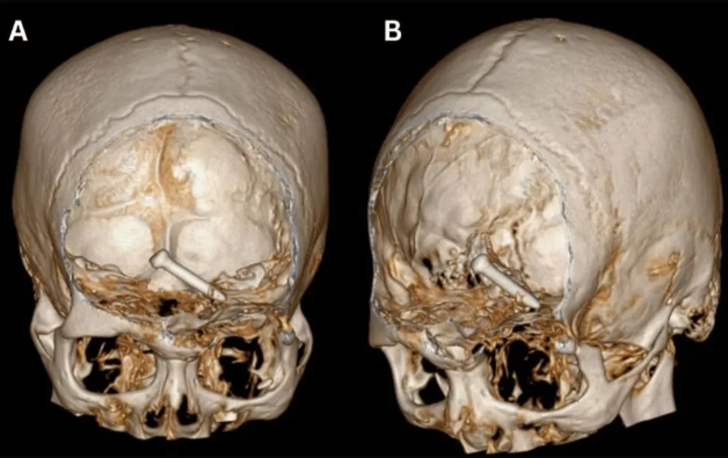

Röntgen görüntüleri, 3,2 cm büyüklüğündeki çivinin, hareket ve konuşma için hayati önem taşıyan beyninin ön lobunun derinliklerine saplandığını gösterdi.

Cureus tıp dergisinde yayınlanan araştırmaya göre, sol gözünün yan kantusunda (iki göz kapağının birleştiği yerde) yaralar ve sol yörünge tavanında ve tabanında kırıklar da vardı. Çalışma, çivinin bir şekilde hayati arterleri ve sinirleri ıskaladığını ve uzun vadeli herhangi bir hasardan kurtulduğunu söyledi. Hasta mucizevi bir şekilde hayatta kalırken görme yeteneğini de kaybetmedi.